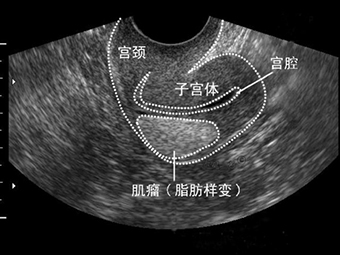

2 子宫肌瘤 不是一切了之

子宫肌瘤有女性生殖健康的“潜在杀手”之称。每3个女性中就有一个子宫肌瘤患者。子宫肌瘤是女性子宫体上长了肌瘤,也被称为子宫平滑肌瘤,是女性生殖器官最常见的良性肿瘤。预防子宫肌瘤,要求妇女在经期及产后要特别注意,严禁房事,保持外阴和阴道清洁,心情舒畅,减轻压力,注意保暖,禁止饮用生水,饮食宜清淡,易消化,忌食辛辣生冷刺激性食物,保持正气充足气血顺畅。

很多女性得了子宫肌瘤,见到医生第一句话就是,给我切了吧。其实不然,治疗子宫肌瘤的方法要视具体情况而定,并非一“切”解千愁。症状轻的患者,若子宫大小不超过孕12周的大小,则不必手术,只要每3个月去医院复查一次,随时注意肌瘤的变化即可。特别是对于近绝经期的患者,因其绝经后肌瘤有自然萎缩的可能,所以一般都主张保守治疗。